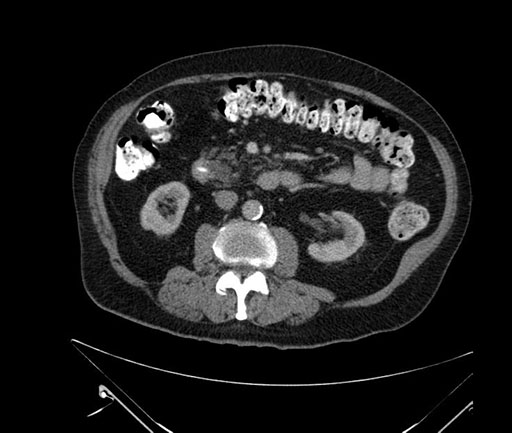

Imaging Analysis

Look through the patient's CT scan to identify any areas of concern for the necessary procedure.

Based on your CT findings, which issue(s) would give reason for "planned slowing down moment(s)" in this case?

Considering a standard Whipple procedure, what step(s) of the operation would you do differently in this case?